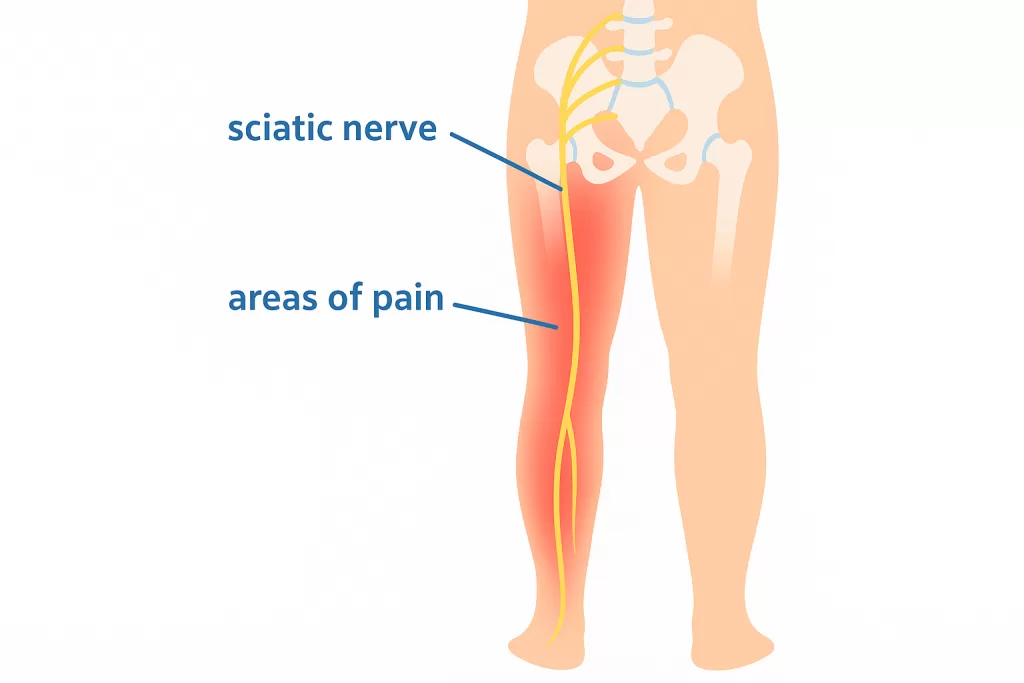

Sciatica

Pain shooting from your lower back down your leg? It could be Sciatica — a nerve condition you shouldn’t ignore. Read more